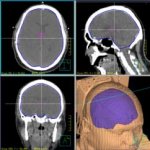

Pinnacle3

放射治療計畫系統:通常叫它英文名TPS,它實際上是一台專為計算放射治療直線加速器輸出劑量分佈的專用電腦,它較人工計算快且準確,能校正組織不均勻性.Philips Pinnacle3 TPS,全球的市場佔有量第一,目前由國霖國際貿易(上海)有限公司中國總代理。在國內各大醫院及96%的腫瘤醫院都採用此計畫系統,主要是該系統平臺高、計算精確度高、系統功能強大(支援各種廠家的IGRT、4D和拉弧調強(Rapid Arc; VMAT)功能。

Pinnacle3是世界上最為廣泛使用的治療計畫系統,其最為突出的特點就是精確、方便和全面,從而自然成為全球大部分用戶首選的三維放療計畫系統。全面整合的光子、電子、立體定向放射治療、近距離放射治療、類比、圖像融合和調強放療(IMRT)等各種選項,使您可以通過單一平臺進行計畫各項治療任務。 Pinnacle³的Collapsed Cone卷積疊加(CCCS)演算法是該行業最準確的、真正的三維劑量計算方法。